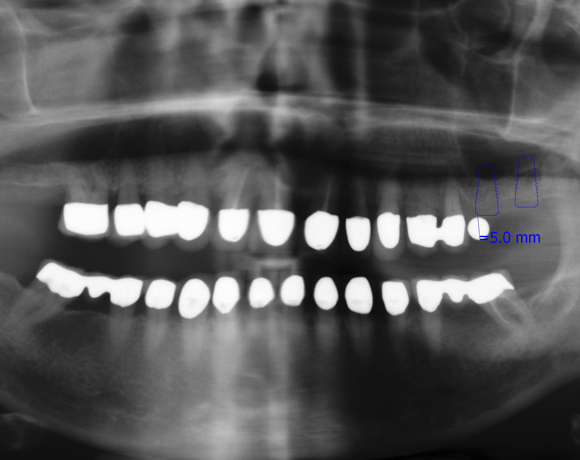

Der vorliegende Patientenfall zeigt eine komplette Neuversorgung der vorhandenen Metallkeramikkronen mit vollkeramischen Restaurationen. Zusätzlich wurde im Oberkiefer die Zahnreihe mit zwei Implantaten, für die fehlenden Molaren, ergänzt. Da keine ausreichende Knochenhöhe vorhanden war wurde ein interner Sinuslift geplant.